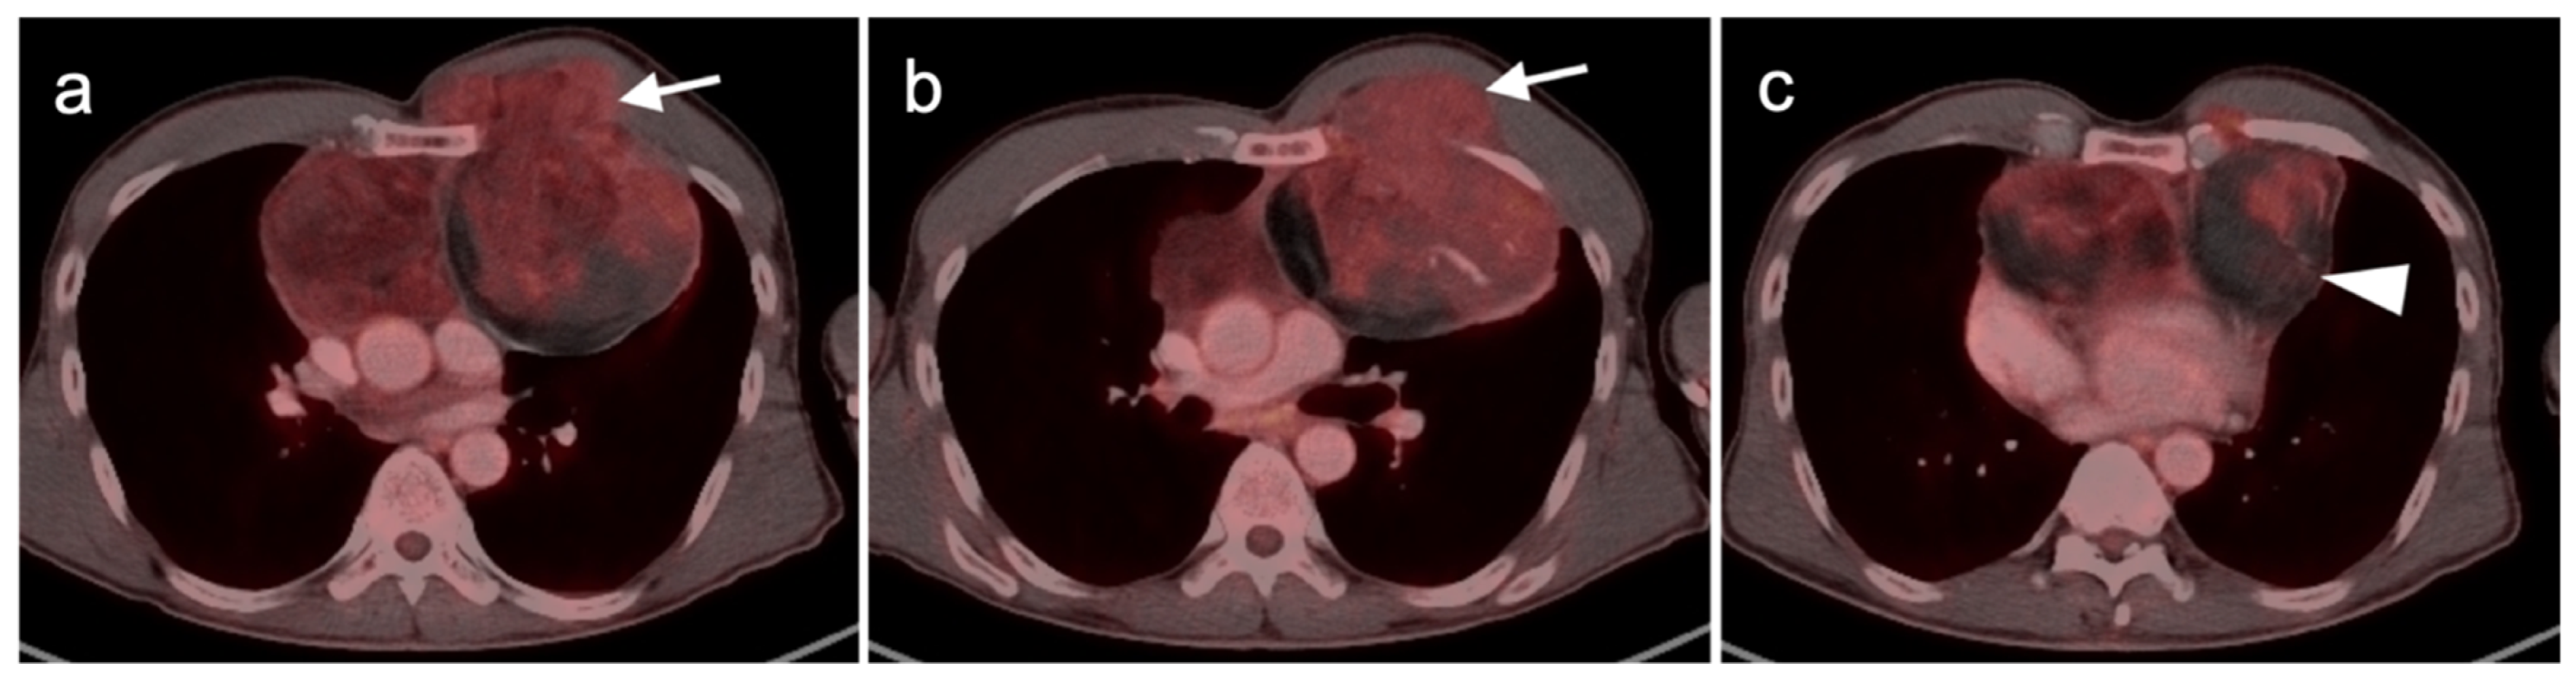

2.4. Merkel Cell Carcinoma

4.4. Bronchial Carcinoid